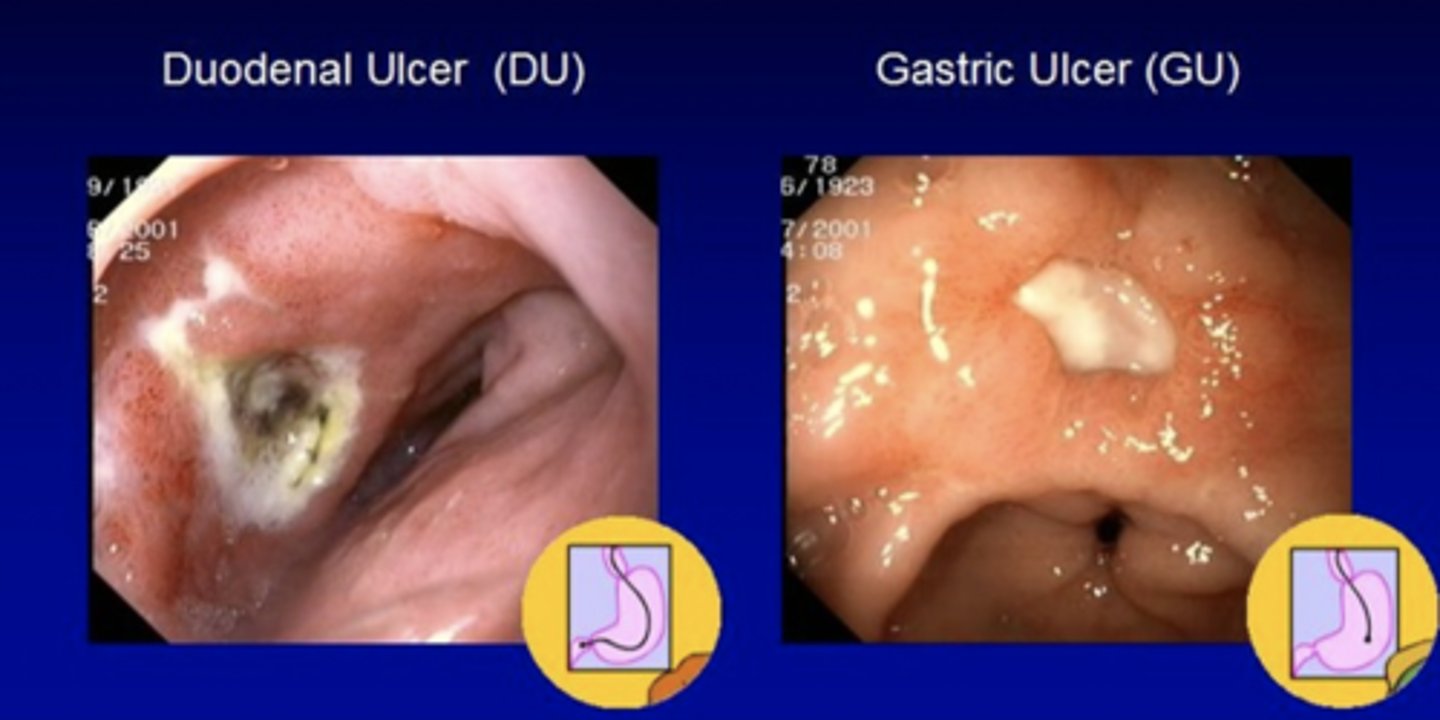

John, a 47-year-old man, presents to the clinic with a 3-month history of intermittent epigastric pain that worsens on an empty stomach and improves after eating. He describes the pain as "gnawing" and sometimes wakes up at night because of it. He has also experienced occasional nausea and bloating, but no vomiting or weight loss. He denies NSAID use or alcohol consumption. Patient is allergic to penicillin. Physical exam reveals mild tenderness in the epigastric region. You order a rapid urease test after conducting an endoscopy with biopsy. Test comes back positive for H. Pylori.

What clinical manifestations would you expect to find in the antrum?

What clinical manifestations would you expect to find in the gastric body?

How do you treat this patient?

You want to test 4 weeks after completion of therapy to see if the medication works and H. Pylori is eradicated. What test do you order?

1. Antrum: increased gastrin -> increased HCl production -> duodenal ulcer

2. Gastric Body: Can disrupt acid secretion and/or destroy acid-secreting cells --> Increased risk of gastric ulcers and gastric cancers

3.) Quadruple therapy for 14 days

PPI + Bismuth + Metronidazole + Tetracycline (Pylera)

4.) Urea Breath Test

Kevin, a 52-year-old man, presents to the clinic with burning epigastric pain that has been occurring for the past 2 months. He describes it as a gnawing, dull, and hunger-like ache that often improves after eating, but returns 2 to 4 hours later. He also mentions that the pain sometimes wakes him up at night. Over the past week, he has noticed dark stools and mild fatigue. He denies NSAID use, but reports daily coffee and alcohol consumption. He has no known history of GI disease. His fecal occult blood test is positive.

1.) What tests do you order?

2.) What is the patient's diagnosis?

3.) How do you treat this patient?

1.) Endoscopy with biopsy.

2.) Peptic Ulcer --> Since symptoms improve after eating this is specifically a duodenal ulcer

3.) PPIs and H2RAs

- Mucosal defense agents such as bismuth sucralfate or misoprostol

What is the most common cause of Upper GI bleeding?

Peptic Ulcer Disease